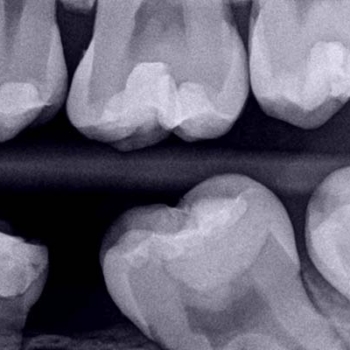

The quality of the definitive restoration and its close adaptation to the dentine structure to prevent leaks are key factors in the long-term success of the procedure. Correct marginal adaptation and the continuity of the restoration with the dental tissue can be seen in the final radiograph of the procedure (Fig. 8). An assessment was made seven days after treatment to ensure that the patient was completely asymptomatic and responded to sensitivity tests in a normal manner. A normal tissue response was obtained in all the tests.

Fig. 8. Final radiograph of the vital pulp therapy procedure. The different layers of materials used, and the correct marginal adaptation can be seen.